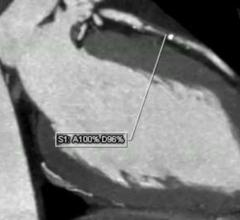

This channel contains news about the Society of Cardiovascular Computed Tomography (SCCT), including coverage of its annual meeting and links to recently released practice guidelines. SCCT is a leading resource for the subspecialty of cardiac computed tomography angiography (CTA or CCTA).

DAIC Editor Dave Fornell explains some of the most innovative new cardiovascular CT technology displayed at the Society ...